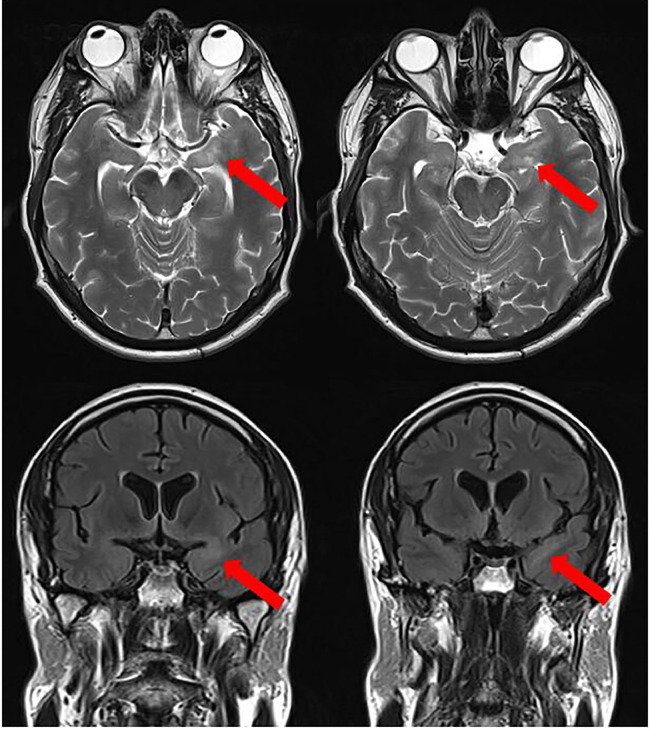

Acute neurosyphilis is a rare but easily treatable cause of subacute confusion. Its clinical presentation is varied, with reported phenotypes ranging from acute stroke-like presentations to psychosis, dementia and meningoencephalitis. Neurosyphilis is easily detectable and treatable, despite its clinical heterogeneity. We present a 45-year-old man without HIV presenting with a subacute encephalitis, with cerebrospinal fluid and blood markers strongly positive for syphilis, with clinical improvement following 2 weeks of empirical intravenous antibiotic therapy.